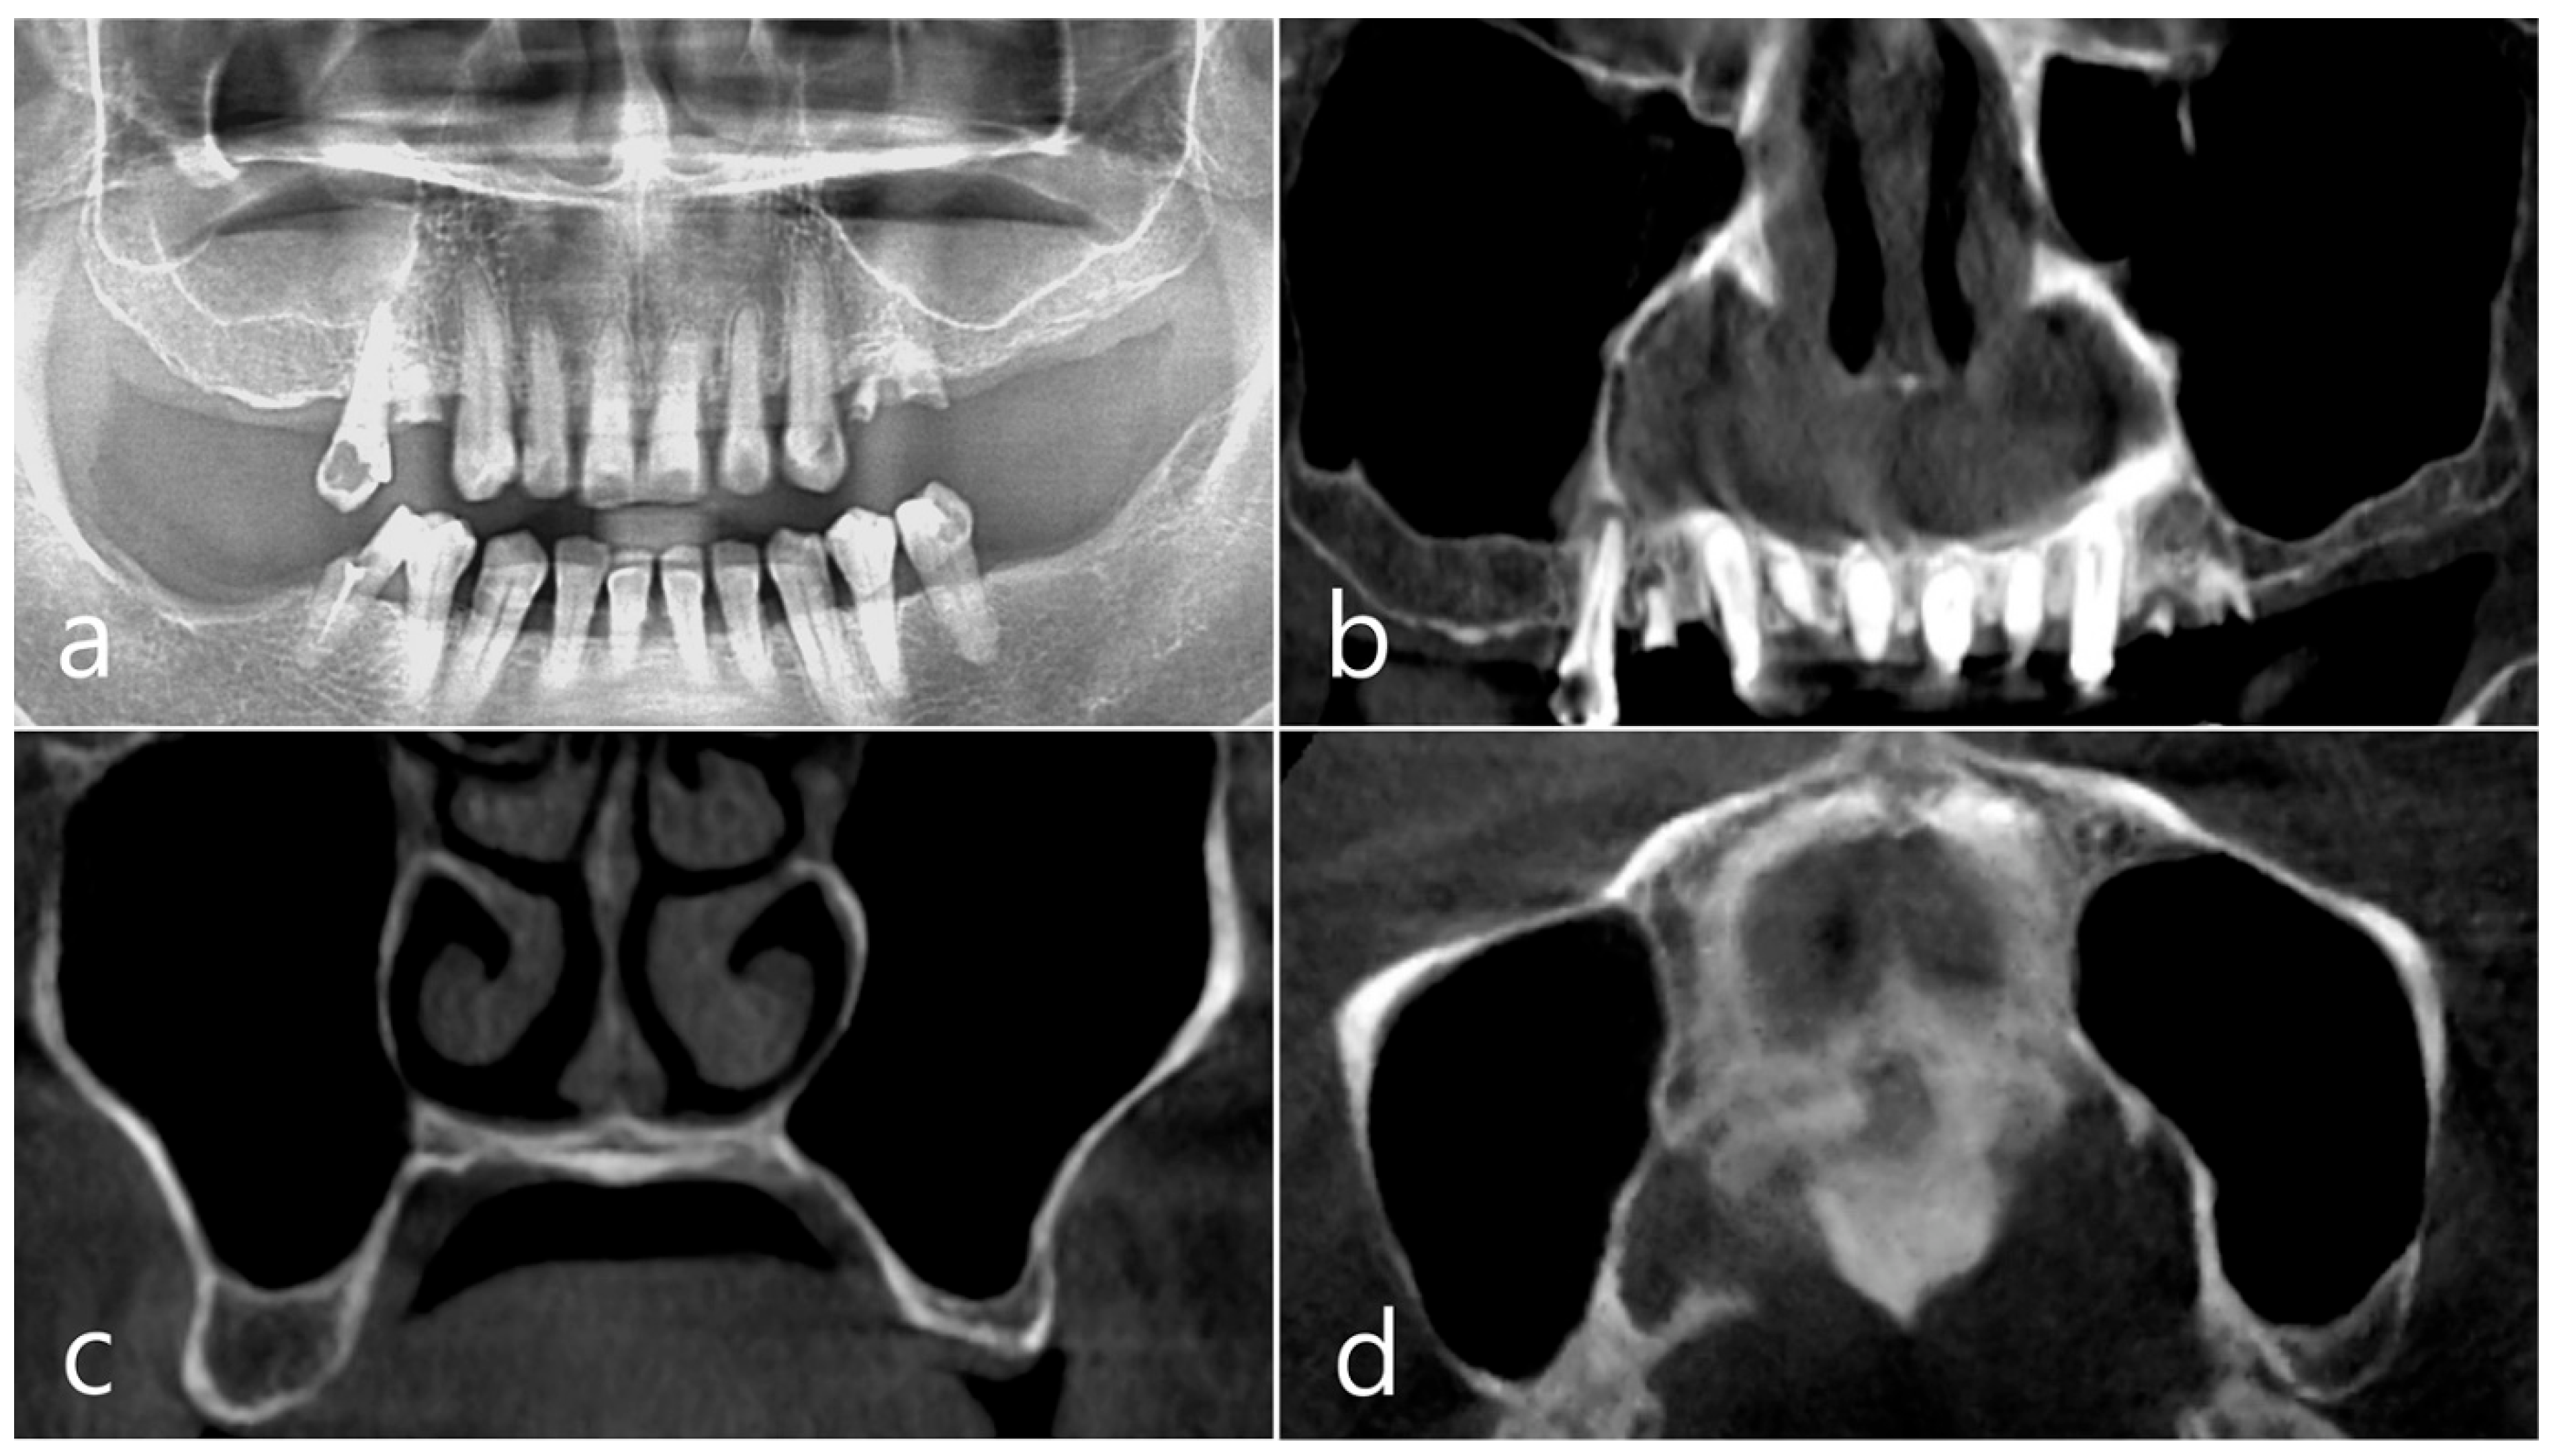

This patient was a 58-year-old male smoker who was taking antihypertensive drugs. The patient visited our clinic for implant placement in the upper left posterior region. Teeth #24 and #25 were determined to be extracted due to severe periodontal disease. In panoramic radiography, the residual alveolar bone was severely atrophied, and pneumatization of the maxillary sinus was severe (Figure 7a). In CBCT imaging, membrane thickening was observed in the sinus floor, but there was no membrane thickening in the rest of the sinus wall (Figure 7b–d).

Figure 7. Case 2. (a,b) On the preoperative panoramic radiography and panoramic image of CBCT, the residual alveolar ridge in the posterior maxilla was severely atrophied and pneumatization of maxillary sinus was severe; (c,d) In CBCT imaging, mucosal thickening (arrows) ranging from 2 to 15 mm was observed in the sinus floor, depending on the location, but there was no mucosal thickening in the rest of the sinus wall.